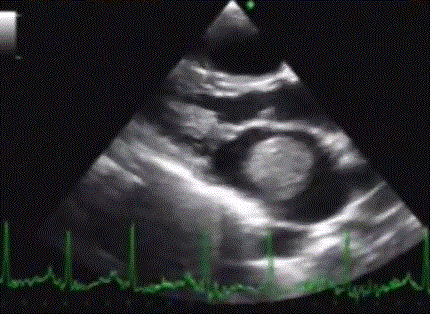

Though PTMC in the presence of LA clot is an option in low risk clots , my strategy would be the last one ,whenever feasible. Intensive, monitored Heparin /Oral anticoagulants ( Heparin 5000 units tds or qid or Low molecular weight heparin Enoxaparin 40-60mg twice a day , Tablet Warfarin /Acitrom with an INR of 3 ) will dissolve LA clot in 30-50% of times.(Our experience).

The percutaneous clot retrieval system is not available as on 2018.Aortic filters are FDA approved during TAVR. (Why not use the same in PTMC ?) LA Catheter based regional lysis through PFO is can be an option if patient agrees to the risk.

How long to wait for clot dissolution with Heparin /OAC?

Most small clots or intermediate sized clots ((Up to 2 CM ?) have been dissolved by 3 months. Even large clots gets dissolved at least in few Instances.Please note, this strategy is applicable only with valves that is fit for PTMC. All others are referred for surgery.